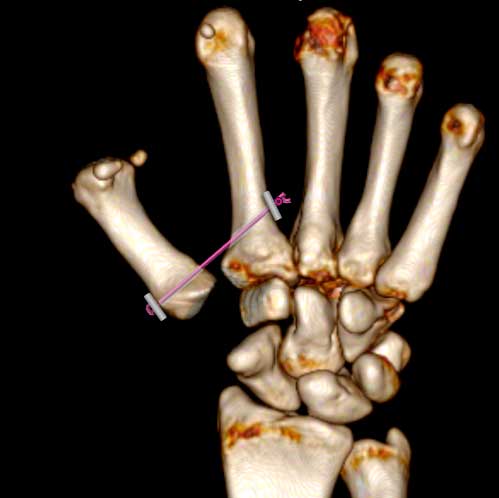

2ª) Extirpación del trapecio y colocación entre primer y segundo metacarpiano de un sistema de suspensión para que el espacio que ha dejado el trapecio se rellene de sangre y tejido fibroso.

Este sistema de suspensión se llama “MiniThighrope” (Arthrex) y evita que el primer metacarpiano “caiga” en el espacio que ha dejado el trapecio. El cual se rellenará de tejido cicatricial y coágulos y actuará como un sistema de amortiguación evitando el roce entre dos huesos y, por tanto, el dolor.

Extirpación del trapecio y colocación entre primer y segundo metacarpiano. Tratamiento 1

colocación de un espaciador entre primer y segundo metacarpiano tras extirpación del trapecio. Trataamiento 2